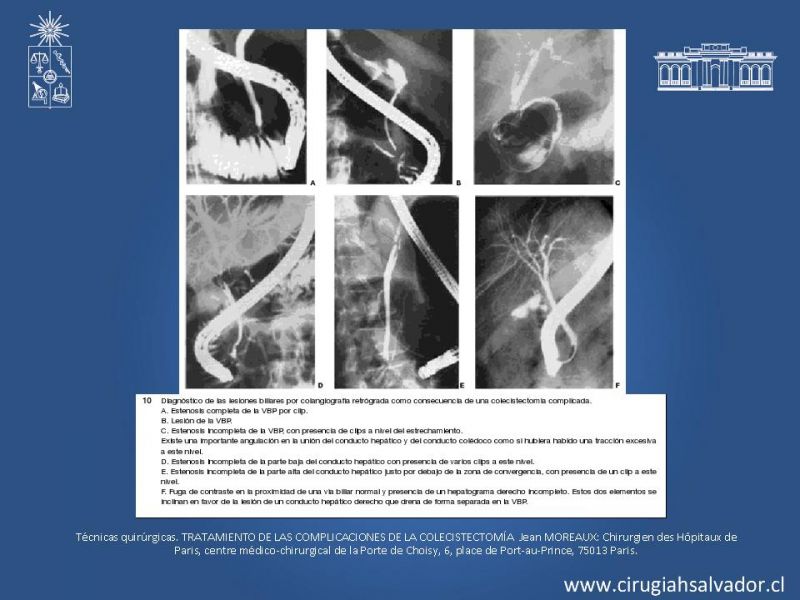

Lesiones quirúrgicas de la vía biliar

Hepatobiliopancreático

| Autor: Julio A. Jiménez Lillo